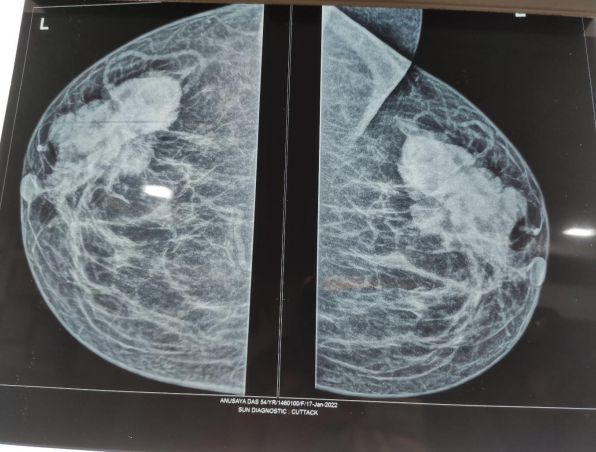

Fig 2. On Mammography- An Irregular Lobulated Large Density Noted in the Upper Outer Quadrant of Left Breast Extending Towards the Retro Areolar Region s/o Suspicious Left Breast Mass Lesion. Few Prominent Nodes with Maintained Fatty Hilum noted in Left Axilla. (BIRADS-IVA)

The primary clinical impression was locally advanced breast cancer. Initial standard investigations included mammogram (Fig. 2), followed by core needle biopsy. Core biopsy was Suggestive of Invasive Ductal carcinoma. (Grade -1)